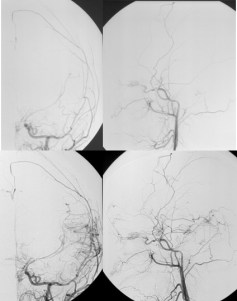

- l’angiographie des 6 axes : elle est nécessaire en pré-opératoire, pour étudier les les anastomoses extra-intra-crâniennes existantes et à respecter, rechercher des anévrysmes

les patients ne font habituellement plus d’AVC en postopératoire. l’artériographie montre une bonne reperfusion cérébrale par les artères du territoire carotidien externe. cependant, si ils sont porteurs d’une maladie vasculaire sous-jacente, celle-ci peut continuer d’évoluer pour son propre compte.